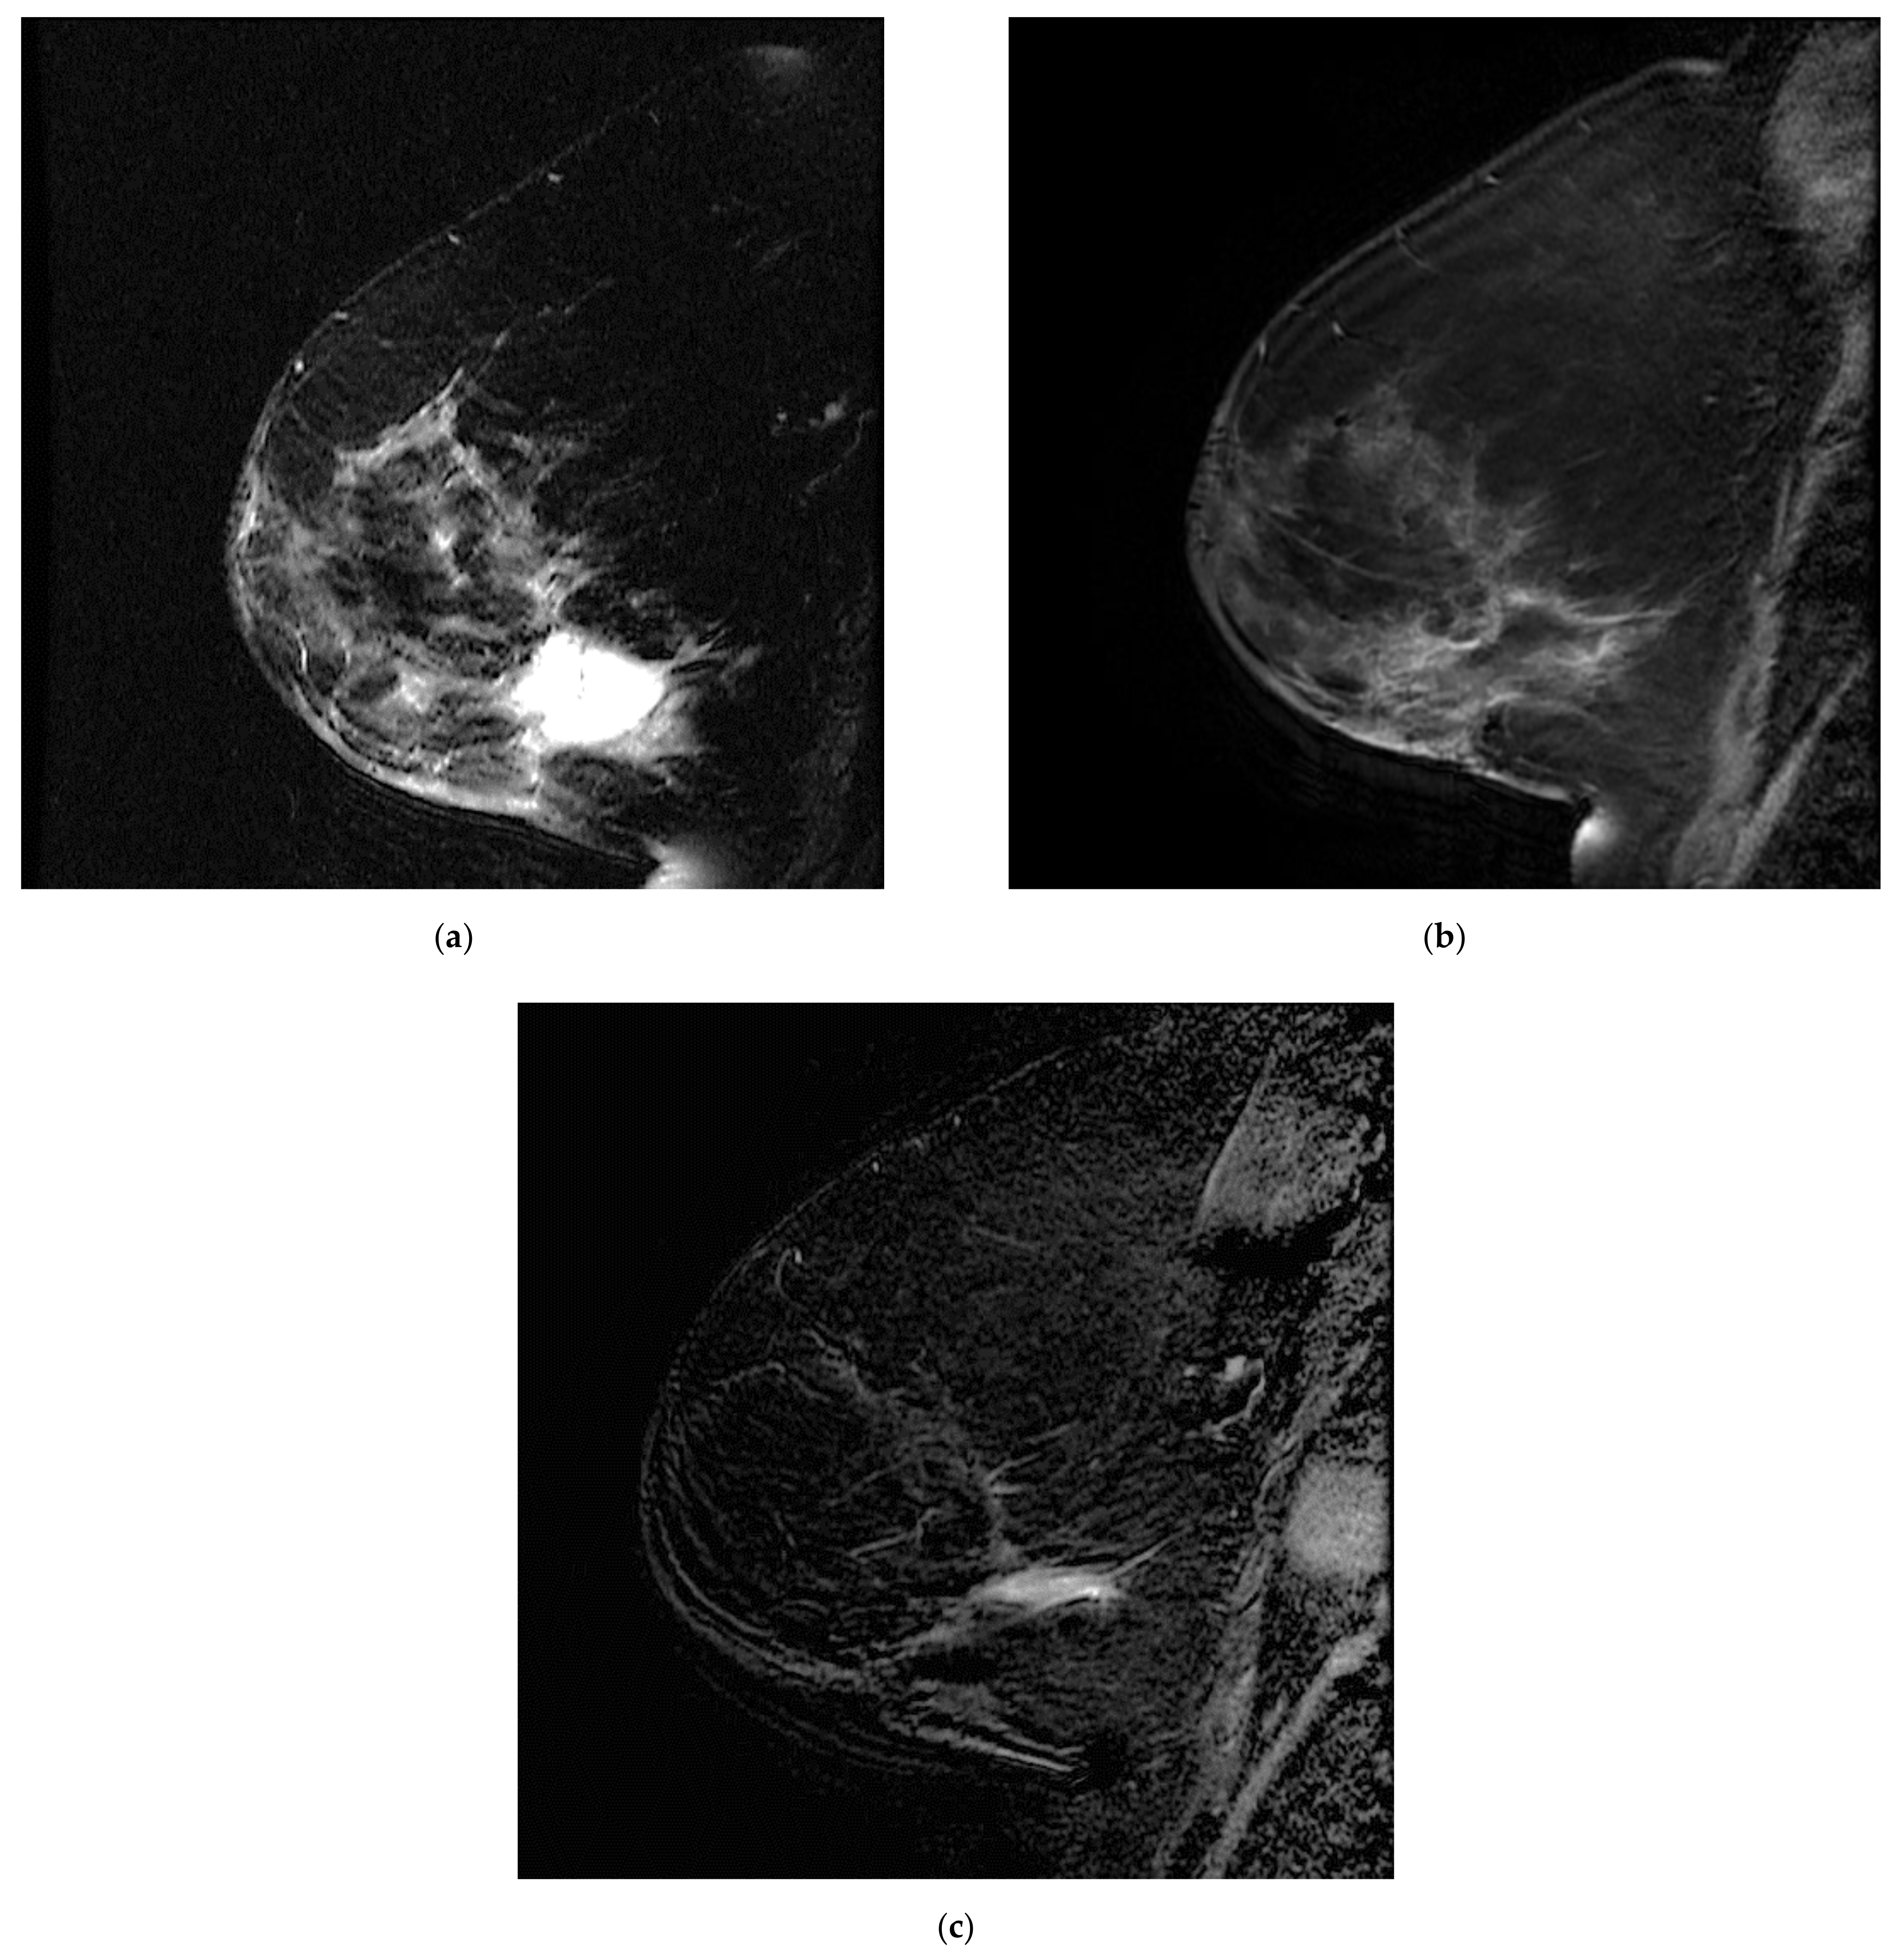

Figure 5.

Postoperative seroma with surrounding non-mass enhancement on MRA (a) T2-weighted sequence and (b) T1 fat sat with gadolinium. The seroma resolved and linear enhancement is seen in the same location on (c) MR B. This was initially attributed to post-surgical changes and later confirmed to correspond to disease recurrence.